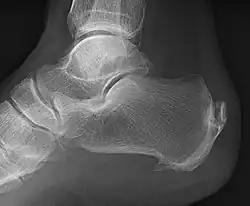

Enthesophyte

Enthesophytes are abnormal bony projections at the attachment of a tendon or ligament.[1] They are not to be confused with osteophytes, which are abnormal bony projections in joint spaces. Enthesophytes and osteophytes are bone responses for stress.[1]